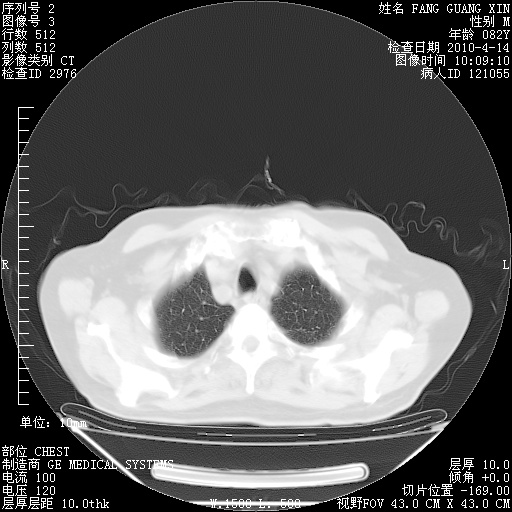

4月14日肺部CT

23.JPG

24.JPG

25.JPG

26.JPG

肺部CT平扫未见异常。